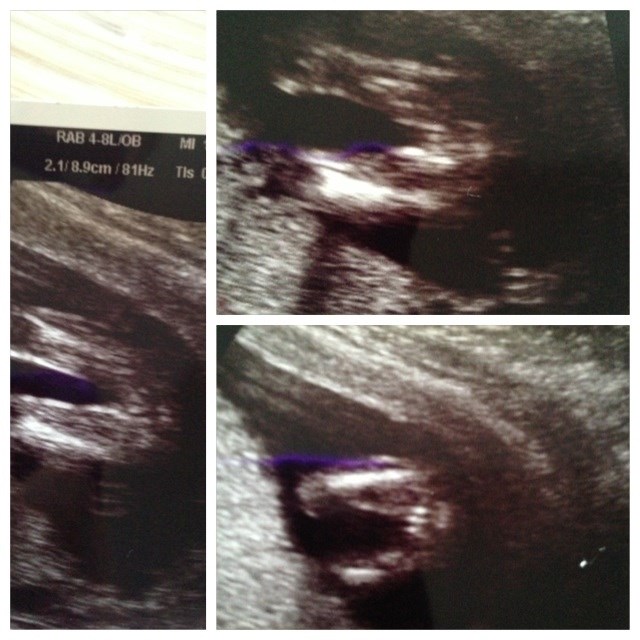

I følge kønsscanningen venter vi en lille pige, men da vi ikke fik noget bekræftet ved md-scanningen kan jeg alligevel ikke lade være med at tvivle lidt

Så hvad siger i? Dreng eller pige?

Vedhæftede fotos (klik for at se i fuld størrelse)